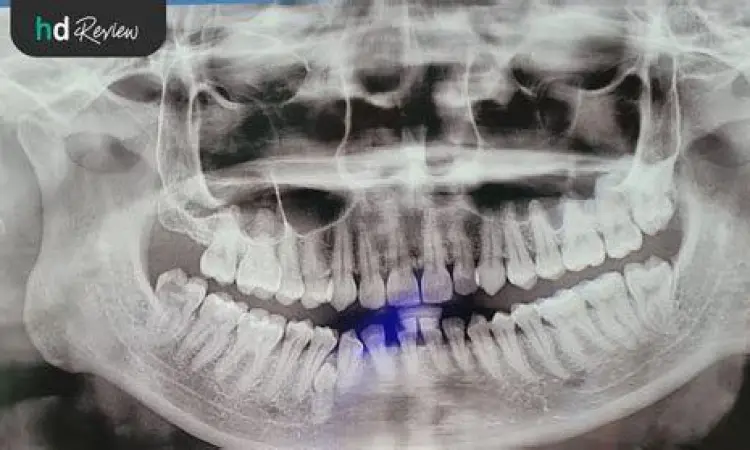

- Rontgen Panoramik dan Cephalometric: Diperlukan untuk melihat struktur tulang rahang dan akar gigi sebelum prosedur dimulai (Estimasi Rp 500.000 - Rp 1.000.000).